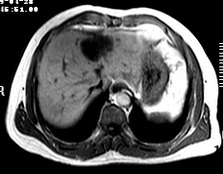

标题: CT19720:肝右叶血管瘤。肝左叶内侧段病灶考虑什么? [打印本页]

标题: CT19720:肝右叶血管瘤。肝左叶内侧段病灶考虑什么?

男,48岁,肝区不适月余,伴隐痛。

支持右叶血管瘤,左叶病灶考虑肝腺瘤。

1)不排除肝左叶肝癌。2)肝右叶血管瘤。

肝左叶炎性病变,肝癌待排。2)肝右叶血管瘤。

1.肝右叶血管瘤;2.肝左叶炎性假瘤?肝癌?建议穿刺活检.

右叶病灶典型,左叶病变慢性炎块

1、肝右叶血管瘤(典型)。

2、肝左叶病灶,强化不明显,疑炎性假瘤,建议结合临床并密切随访。

1、肝左叶炎性病变,肝癌待排。

2、肝右叶血管瘤。

肝左叶脓肿,肝癌待排。2)肝右叶血管瘤